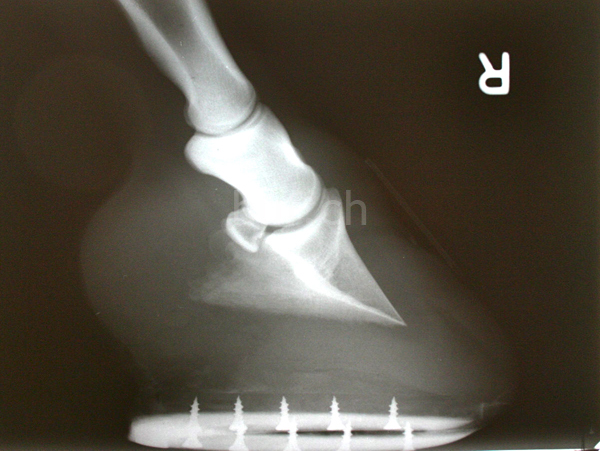

Meist sind die Hinterhufe stärker abgenutzt als die vorderen. Dadurch kann man schnell zu dem Schluss gelangen, dass das Pferd das Gewicht eher auf die Hinterhand verlagert. Diese Verlagerung wäre dann ein Anzeichen der vielleicht seit Jahren angestrebten Versammlung, genau hier aber liegt der Fehler.

Die Abnutzung des Hufs ist anatomisch bedingt. In der Regel setzt das Pferd den Hinterhuf zu einer Schiebebewegung auf den Boden auf. Der stärkere Druck führt in der Folge zu einer stärkeren Abnutzung. Beziehen Sie dieses Phänomen also in Ihre Überlegungen zu einer Hufkorrektur mit ein.

Das Abfussen

Beim Abfußen werden die vorderen Hufe im Zehenbereich stärker abgenutzt als die hinteren. Die Abnutzung entsteht durch die Reibung der Zehenspitze beim Abfußen gegen den Boden: Dieses Phänomen nennt man Zehenrichtung. Sie entsteht stellungsunabhängig meistens etwas seitlich von der Hufspitze. Steilere Hufe haben dabei durch den spitzeren Winkel eine stärker abgenutzte Zehenrichtung als flachere Hufe.

Die Korrektur der Zehenrichtung zur Mitte hin ist sinnlos, da sie anatomisch bedingt ist. Sie kann nicht durch Anfeilen des Barhufs oder mit einem Spezialbeschlag bestimmt werden. Versucht man die Zehenrichtung künstlich zu ändern, wird lediglich die Abrollmechanik des Pferdes gestört. Unterstützen lässt sie sich dagegen, indem man den Radius der Zehenrichtung vergrößert.